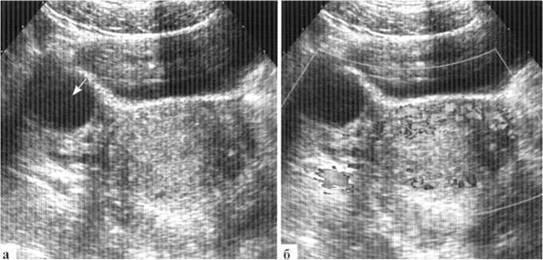

В норме визуализировать внутренние гениталии у новорожденной девочки удается не всегда, в основном из-за недостаточного наполнения мочевого пузыря ребенка на момент осмотра. В то же время, высокое расположение яичников у новорожденной делает возможным их визуализацию иногда и при опорожненном мочевом пузыре, даже из доступов в подвздошных областях. В некоторых случаях яичник на УЗИ определяется непосредственно под прямой мышцей живота. Строение внутренних гениталий новорожденной весьма вариабельно: яичники в норме могут иметь размеры как 6*Х мм с недифференцированными фолликулами, так и 35x25 мм с множественными фолликулами по 5—8 мм в диаметре (рис. 1.1).

Рис. 1.1. УЗ-варианты нормы яичников у новорожденных: а — яичники определяются is типичном месте при почти опорожненном мочевом пузыре; крупные (20x13 мм, мультифолликулярные); б — правый яичник мультифолликулярный, расположен высоко, около дна мочевого пузыря

Количество фолликулов в яичниках новорожденных может быть различным, достигая 10 и более в одном скане, при этом дальнейшее половое развитие девочек в течение первого года жизни протекает без особенностей. Такие мультифолликулярные яичники относительно часто наблюдаются у девочек, которые находятся на грудном вскармливании, что позволяет предположить роль материнского гормонального фона (рис. 1.2).

Рис. 1.2. Гиперстимулировнные яичники новорожденной: расположены высоко, рядом с боковой стенкой мочевого пузыря, по размером яичник сопоставим с мочевым пузырем